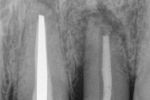

Nonsurgical retreatment of a postsurgical endodontic failure.

Autor(en): Kleier DJ.

Fundstelle: J Endod 1984; 10: 577–579

A 45-yr-old Caucasian woman was referred by her family dentist because of pain and periapical pathology associated with both her maxillary central incisors. The teeth had been endodontically treated and retrofill amalgams had been placed. Both teeth were diagnosed as postsurgical endodontic failures. The teeth were retreated nonsurgically. An 18-month recall examination showed normal soft tissue anatomy and an apparent decrease in the size of the periapical radiolucencies. Nonsurgical retreatment of postsurgical endodontic failures is an alternative to reoperation or extraction.